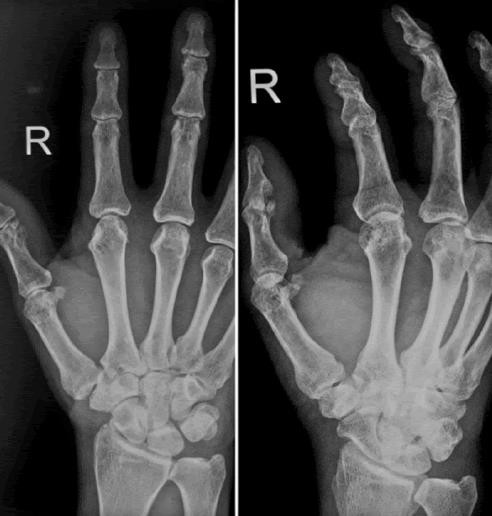

Joshi’s external stabilization system or Kirschner-wire removal was done at 3 to 6 weeks interval with immediate vigorous mobilization of the immobilized joint to avoid stiffness. Functional outcome was assessed based on the total active range of movement in degrees of each injured finger separately.

Only 66.7% of the patients in group A had stable fixation as compared to 90% of the patients in group B. This difference in stability of the fixation was statistically significant.

50% of the patients of group B were found to have complete extension at the MCP joint in comparison to 13.3% of the group A patients where complete extension was achieved. 3.3% of the patients of group A were found to have a 5° extension lag as compared to 13.3% in group B. The extension lag was found to be 10° for 20% of group A and 13.3% of group B patients. Most patients of group A were found to have an extension lag of 20° in group A as compared to 13.3% patients of group B. An equal incidence of 10% was found between the two groups for an extension lag of 30°. Further, 13.3%, 6.7% and 10% of extension lag of 40°, 50° and 60° respectively was found in patients of group A. This difference in extension lag was statistically significant between the two groups.

The mean flexion in Group A patients was 75.5 degrees and group B patients was 83.67 degrees. This difference in flexion was statistically significant between the two groups.

Only 26.7% of the patients in group A as compared to 60% in group B had excellent results. The study revealed a poor outcome in 13.3% of the group A and 10% of the group B patients. This difference in outcome was statistically significant between the two groups.